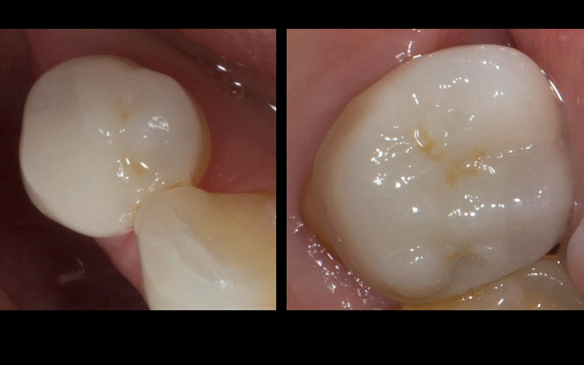

- Poor marginal fit and poor appearance of crowns and bridgework

- Yellowing teeth

The clinical situation and treatment process is shown in detail below with photographs. I (Finlay Sutton) provided the clinical work and Rowan Garstang provided the technical work.